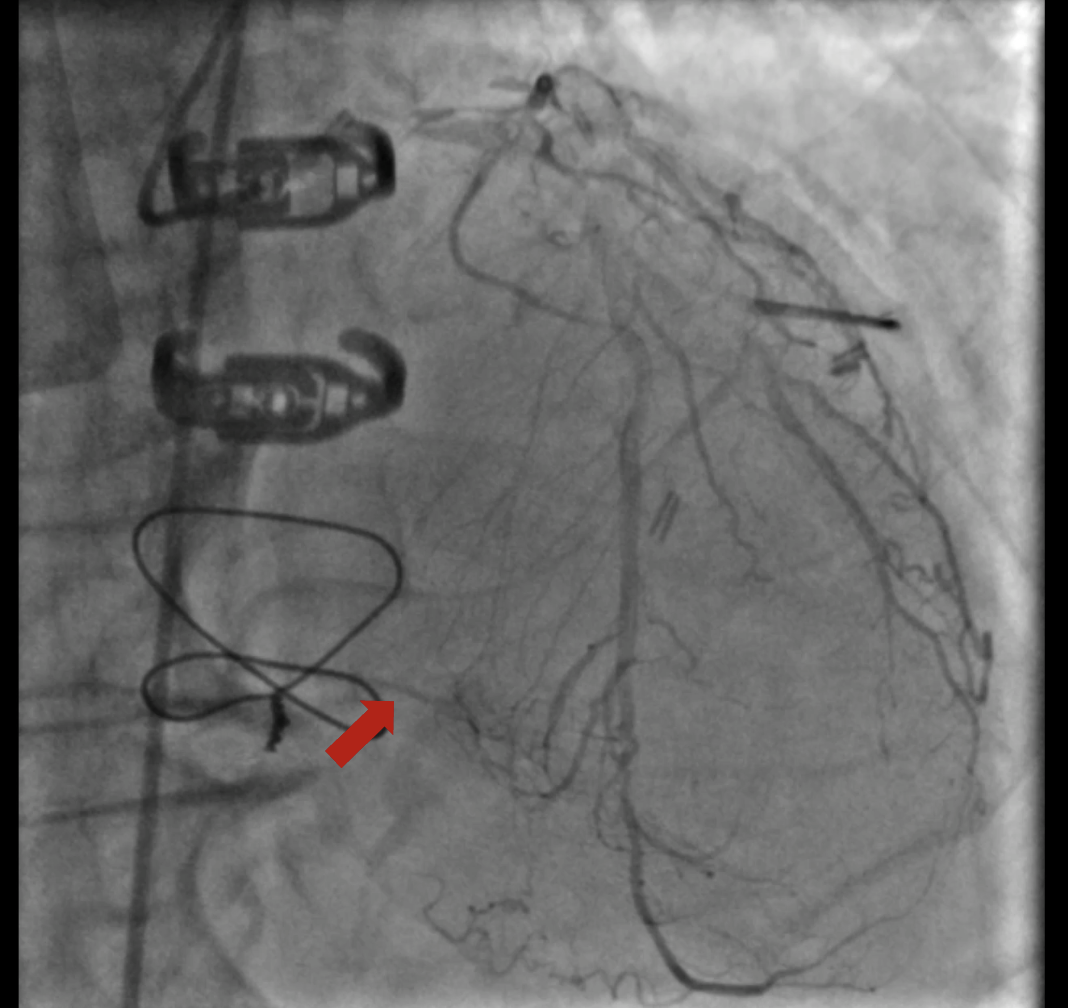

At the 1st encounter, RCA CTO PCI was performed with a plan for staged PCI of the left system. Using a 7F AL 0.75 for strong support, an antegrade approach with a double-lumen microcatheter and parallel wire technique (Pilot 150) successfully crossed the lesion. Predilatation with a 1.5 ¡¿ 15 mm balloon was done. IVUS could not pass due to 360¡Æ calcification. Rotablation with a 1.25 mm burr was attempted but limited to mid-RCA. Two DES were implanted from mid to proximal RCA, followed by post-dilatation.At the 2nd encounter, RCA stents were patent. PCI was done on LM, LAD, and D2. D2 was treated with DCB. LAD predilatation followed by OCT showed severe 330¡Æ calcification (max thickness 1.04 mm, MLA 1.63 mm©÷). IVL with a 2.75 ¡¿ 12 mm balloon (30 pulses) achieved multiple calcium fractures. A 2.75 ¡¿ 33 mm DES was deployed with good OCT results.At the 3rd encounter, 6 months later, the patient presented with ADHF. Angiography revealed RCA ISR CTO at the mid-bending site. The lesion was crossed with a Pilot 200 wire; predilatation showed a dog-bone sign. We do balloon based strategy for plaque modification using cutting, scoring, and double-wire balloons. IVUS showed stent underexpansion with 270¡Æ calcification and distal RCA stenosis. IVL with 2.5 and 2.75 mm balloons optimized the lesion, followed by two DES from distal to mid RCA. Post-PCI IVUS confirmed good result.